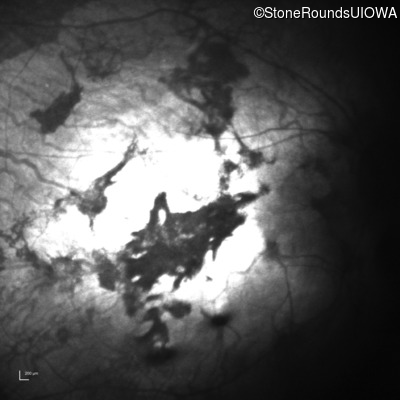

Infrared Fundus Photograph - Left - Light Perception

Exemplar